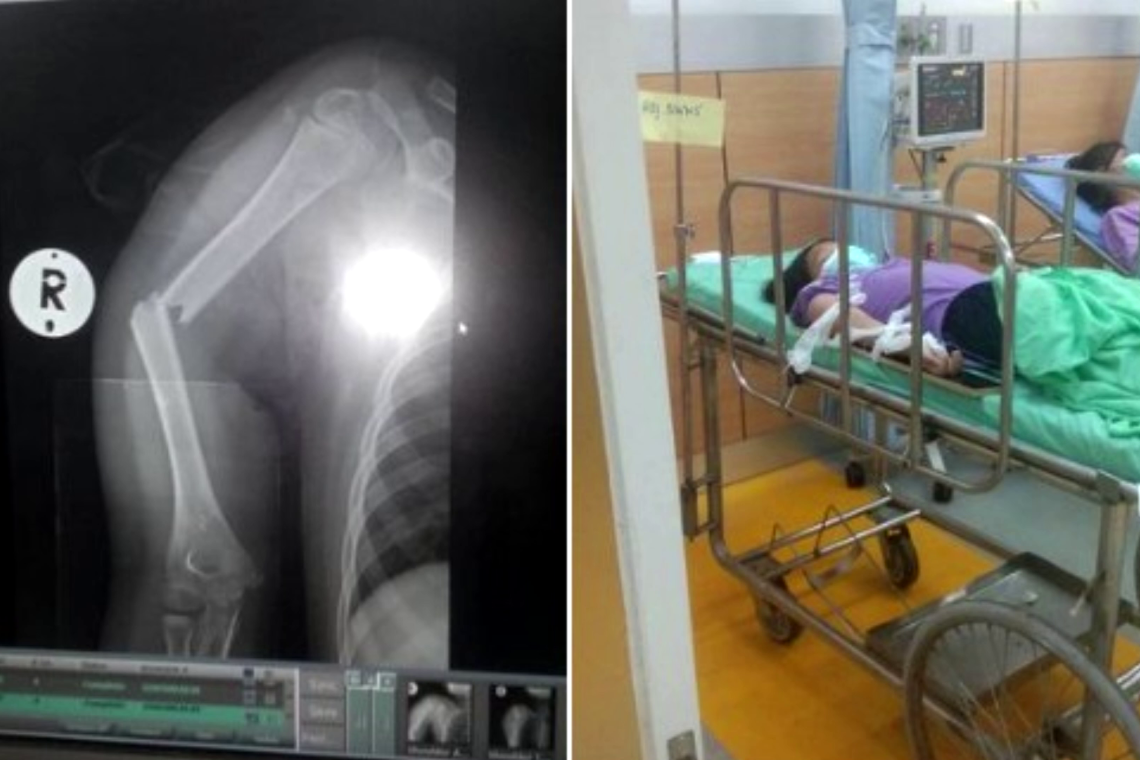

ต่อมาผู้สื่อข่าวจึงติอต่อเข้าสอบถามกรณีดังกล่าว นายศมกร ไชยสุรินทร์ อายุ 69 ปี คุณตาและนายวัชรากร ไชยวาน อายุ 33 ปี คุณน้า เปิดเผยว่า ก่อนอื่นต้องขอออกตัวไว้ก่อนว่าอุบัติเหตุครั้งนี้เราไม่ได้โทษโรงเรียน เพียงแต่เรามีความรู้สึกคาใจว่าเด็กที่ประสบอุบัติเหตุควรจะได้รับการดูแลเร่งด่วนและอย่างดี เด็กประสบอุบัติเหตุได้รับบาดเจ็บแขนหัก แต่กลับให้คุณตาไปรับเพื่อส่งโรงพยาบาล ซึ่งทันที่ที่พาตัวเด็กไปถึงโรงพยาบาลเจ้าหน้าที่พยาบาลเห็นยังบอกเลยว่าเด็กมีแขนผิดรูป รีบนำไปเอกซเรย์ดูรีบตรวจดูทันที ล่าสุดอาการของหลาน แขนยังบวมมีอาการผิดรูป กำลังรอแพทย์ผ่าตัด และมีอาการเจ็บแผลมาก ซึ่งโรงเรียนได้ให้ครูเข้าไปเยี่ยมแล้วที่โรงพยาบาลอุดรธานี